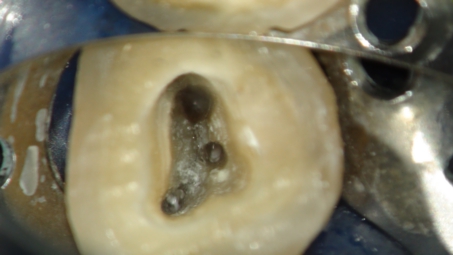

マイクロスコープ

根管治療にはマイクロスコープは必須です

さて、この3)を可能にするのがマイクロスコープによる根管治療です。

狭くて暗い根管の中を適切に清掃し、感染の除去を行う場合、20倍以上に拡大して観察が出来、診ている術者の視線の軸と光の軸が一致し、完全に見えるのがマイクロスコープです。

逆にマイクロスコープなくての根管治療は、暗闇の中で手探りで掃除をしているようなもので、上手くいく方が不思議に思えるような処置であると言っても過言では無いと思います。

You can only treat what you can see.

見えるものしか治療できない

当院ではマイクロスコープを用いた精密な根管治療を行っております。